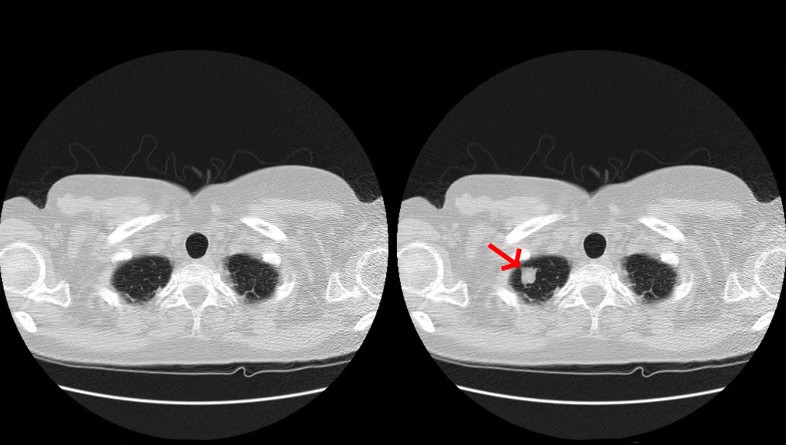

Concretamente, tras alterar hasta 70 tomografías, el equipo ha logrado mentir a tres radiólogos expertos en test ciegos puesto que lo que ataca el malware es la imagen que envía el tac al profesional. En el caso de tumores fabricados, los radiólogos identificaron cáncer el 99 por cientos de las ocasiones, y en el caso de que los signos de cáncer fueran eliminados de pacientes que sí lo padecían, los radiólogos fueron engañados en el 94% de las veces.

El estudio abarca ejemplos de cáncer de pulmón, pero un ataque como el que imagina este malware funcionaría igualmente para tumores cerebrales, enfermedades cardiacas, coágulos sanguíneos, lesiones de la columna vertebral, lesiones de ligamentos, artritis y fracturas óseas.